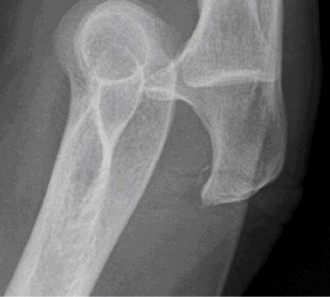

It should be noted that reverse total shoulder arthroplasty is also the procedure of choice in patients with cuff-tear arthropathy (aka rotator cuff arthropathy). Characteristics of cuff-tear arthropathy include superior migration of the humerus due to a massive rotator cuff tear, glenohumeral joint destruction, subchondral osteoporosis, and humeral head collapse (see Fig. 2–17). A reverse total shoulder

Figure 2–17_X-rays of a patient showing evidence of cuff tear arthropathy. The humerus is migrated superiorly, the glenohumeral joint is destroyed, there is subchondral osteoporosis, and the humeral head is collapsed. (From Ecklund KJ, Lee TQ, Tibone J, Gupta R. Rotator cuff tear arthropathy. _J Am Acad Orthop Surg. 2007;15(6):340–349.)